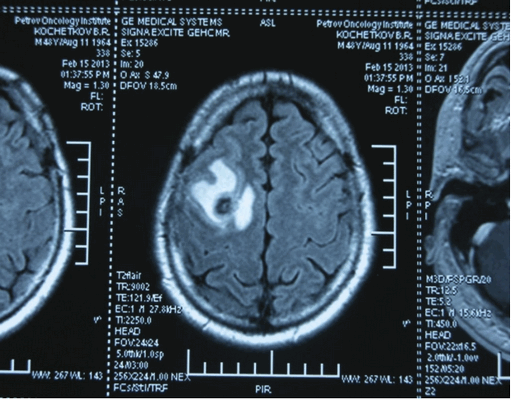

Как дополнительная диагностическая процедура, может быть использована магнитно-резонансная томография головного мозга.

- КТ (расшифровка: компьютерная томография), МРТ (расшифровка: магнитно-резонансная томография), ПЭТ-КТ (расшифровка: позитронно-эмиссионная томография, совмещенная с КТ). Эти обследования необходимы, чтобы рассмотреть структуры организма послойно и визуализировать опухоль. Они показывают, как сильно распространен патологический опухолевый процесс на находящиеся рядом ткани и органы, есть ли поражение костей. КТ - это самый чувствительный метод для обнаружения метастазов в легких. Проведение МРТ и КТ головного мозга необходимо, чтобы обнаружить и визуализировать герминогенные новообразования эпифиза.

Рисунок 7. - Герминома головного мозга.